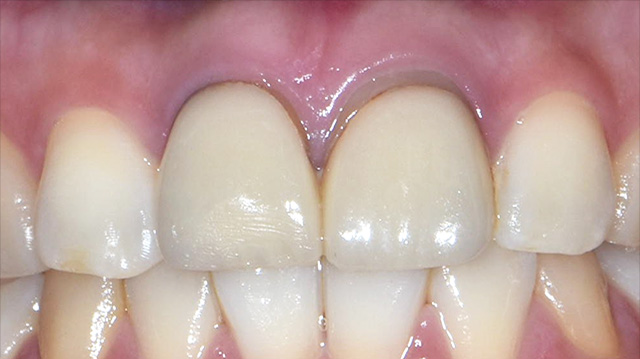

| 年代・性別 | 40代 男性 |

|---|---|

| 主訴 | 前歯の被せ物が取れた |

| 治療回数 | 3回 |

| 治療期間 | 約1ヶ月 |

| 費用 | 仮歯 5,500円 ジルコニアクラウン 176,000円 |